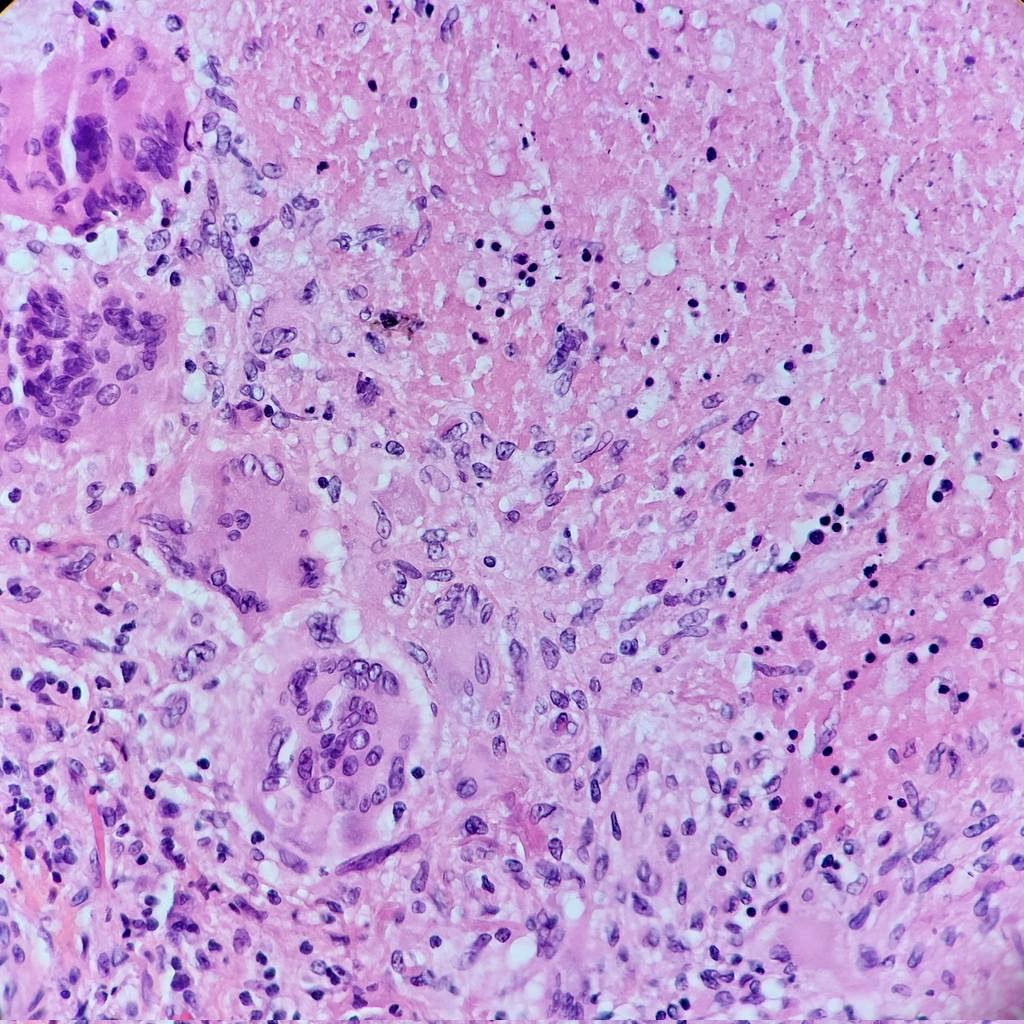

- 1Central caseous necrosis

- 2Epithelioid histiocytes with elongated nuclei

- 3Langhans giant cells with peripheral nuclear arrangement

- 4Lymphocytic cuff

- Central caseous (cheese-like) necrosis — amorphous eosinophilic acellular material

- Langhans giant cells: peripheral horseshoe arrangement of nuclei

- Surrounding epithelioid macrophages (transformed from monocytes)

- Rim of lymphocytic infiltration around the granuloma